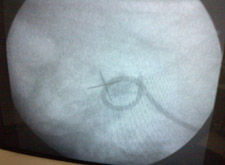

The lithotripsy procedure is done in a lithotripsy specialised centre and takes about an hour to be done. This is done on the same day care basis, usually without anaesthesia. Some analgesia and sedation may be given to allay the patient's anxiety and make him relax or go to sleep. The stone is localised with high frequency digital C-arm and the shock waves are focused on the stone. The patient may feel a tapping sensation during the procedure. If a large stone fragment remains after treatment a second sitting may be required after 7 – 10 days.

Lithotripsy is usually safe for patients from the age of 2 years on wards. Absolute contraindications include pregnancy and bleeding disorders. Patients on blood thinners need to stop them for at least 5 days prior to the procedure. Depending upon certain factors a D-J Stent may be inserted prior to the procedure which is temporary and would be removed after some days .Stones in non functioning kidneys are obviously not suitable for this procedure as the stone fragments will not pass out. Anatomical obstructions of the urinary tract distal to the calculi may need additional treatment.